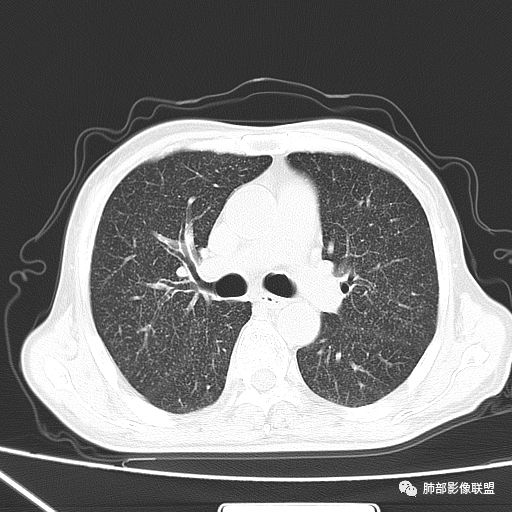

2019年9月12日CT(外院片,手机拍摄)

2019-10-20复查CT如下:

两肺弥漫性粟粒样结节伴左上肺小结节,呈三均匀分布,有结核的临床表现,支持血性播散性肺结核。

大小、分布均匀,边缘清楚

细小结节,弥漫,撒米粒样——血道来源

血道来源的病灶,均匀、细微,而且部分有分支状,都符合粟粒型肺结核

急性血行播散型肺结核  两肺广泛分布粟粒大小的结节状密度增高影,具有大小均匀、分布均匀、密度均匀的典型“三均匀”特征,注意急性血播病灶非常小,一般粟粒影直径1~2mm。

病灶密集者出现肺外围血管影不清或减少。

发热初期肺部可缺乏典型影像学改变,1到2周后出现的广泛粟粒结节对诊断具有高度提示作用!